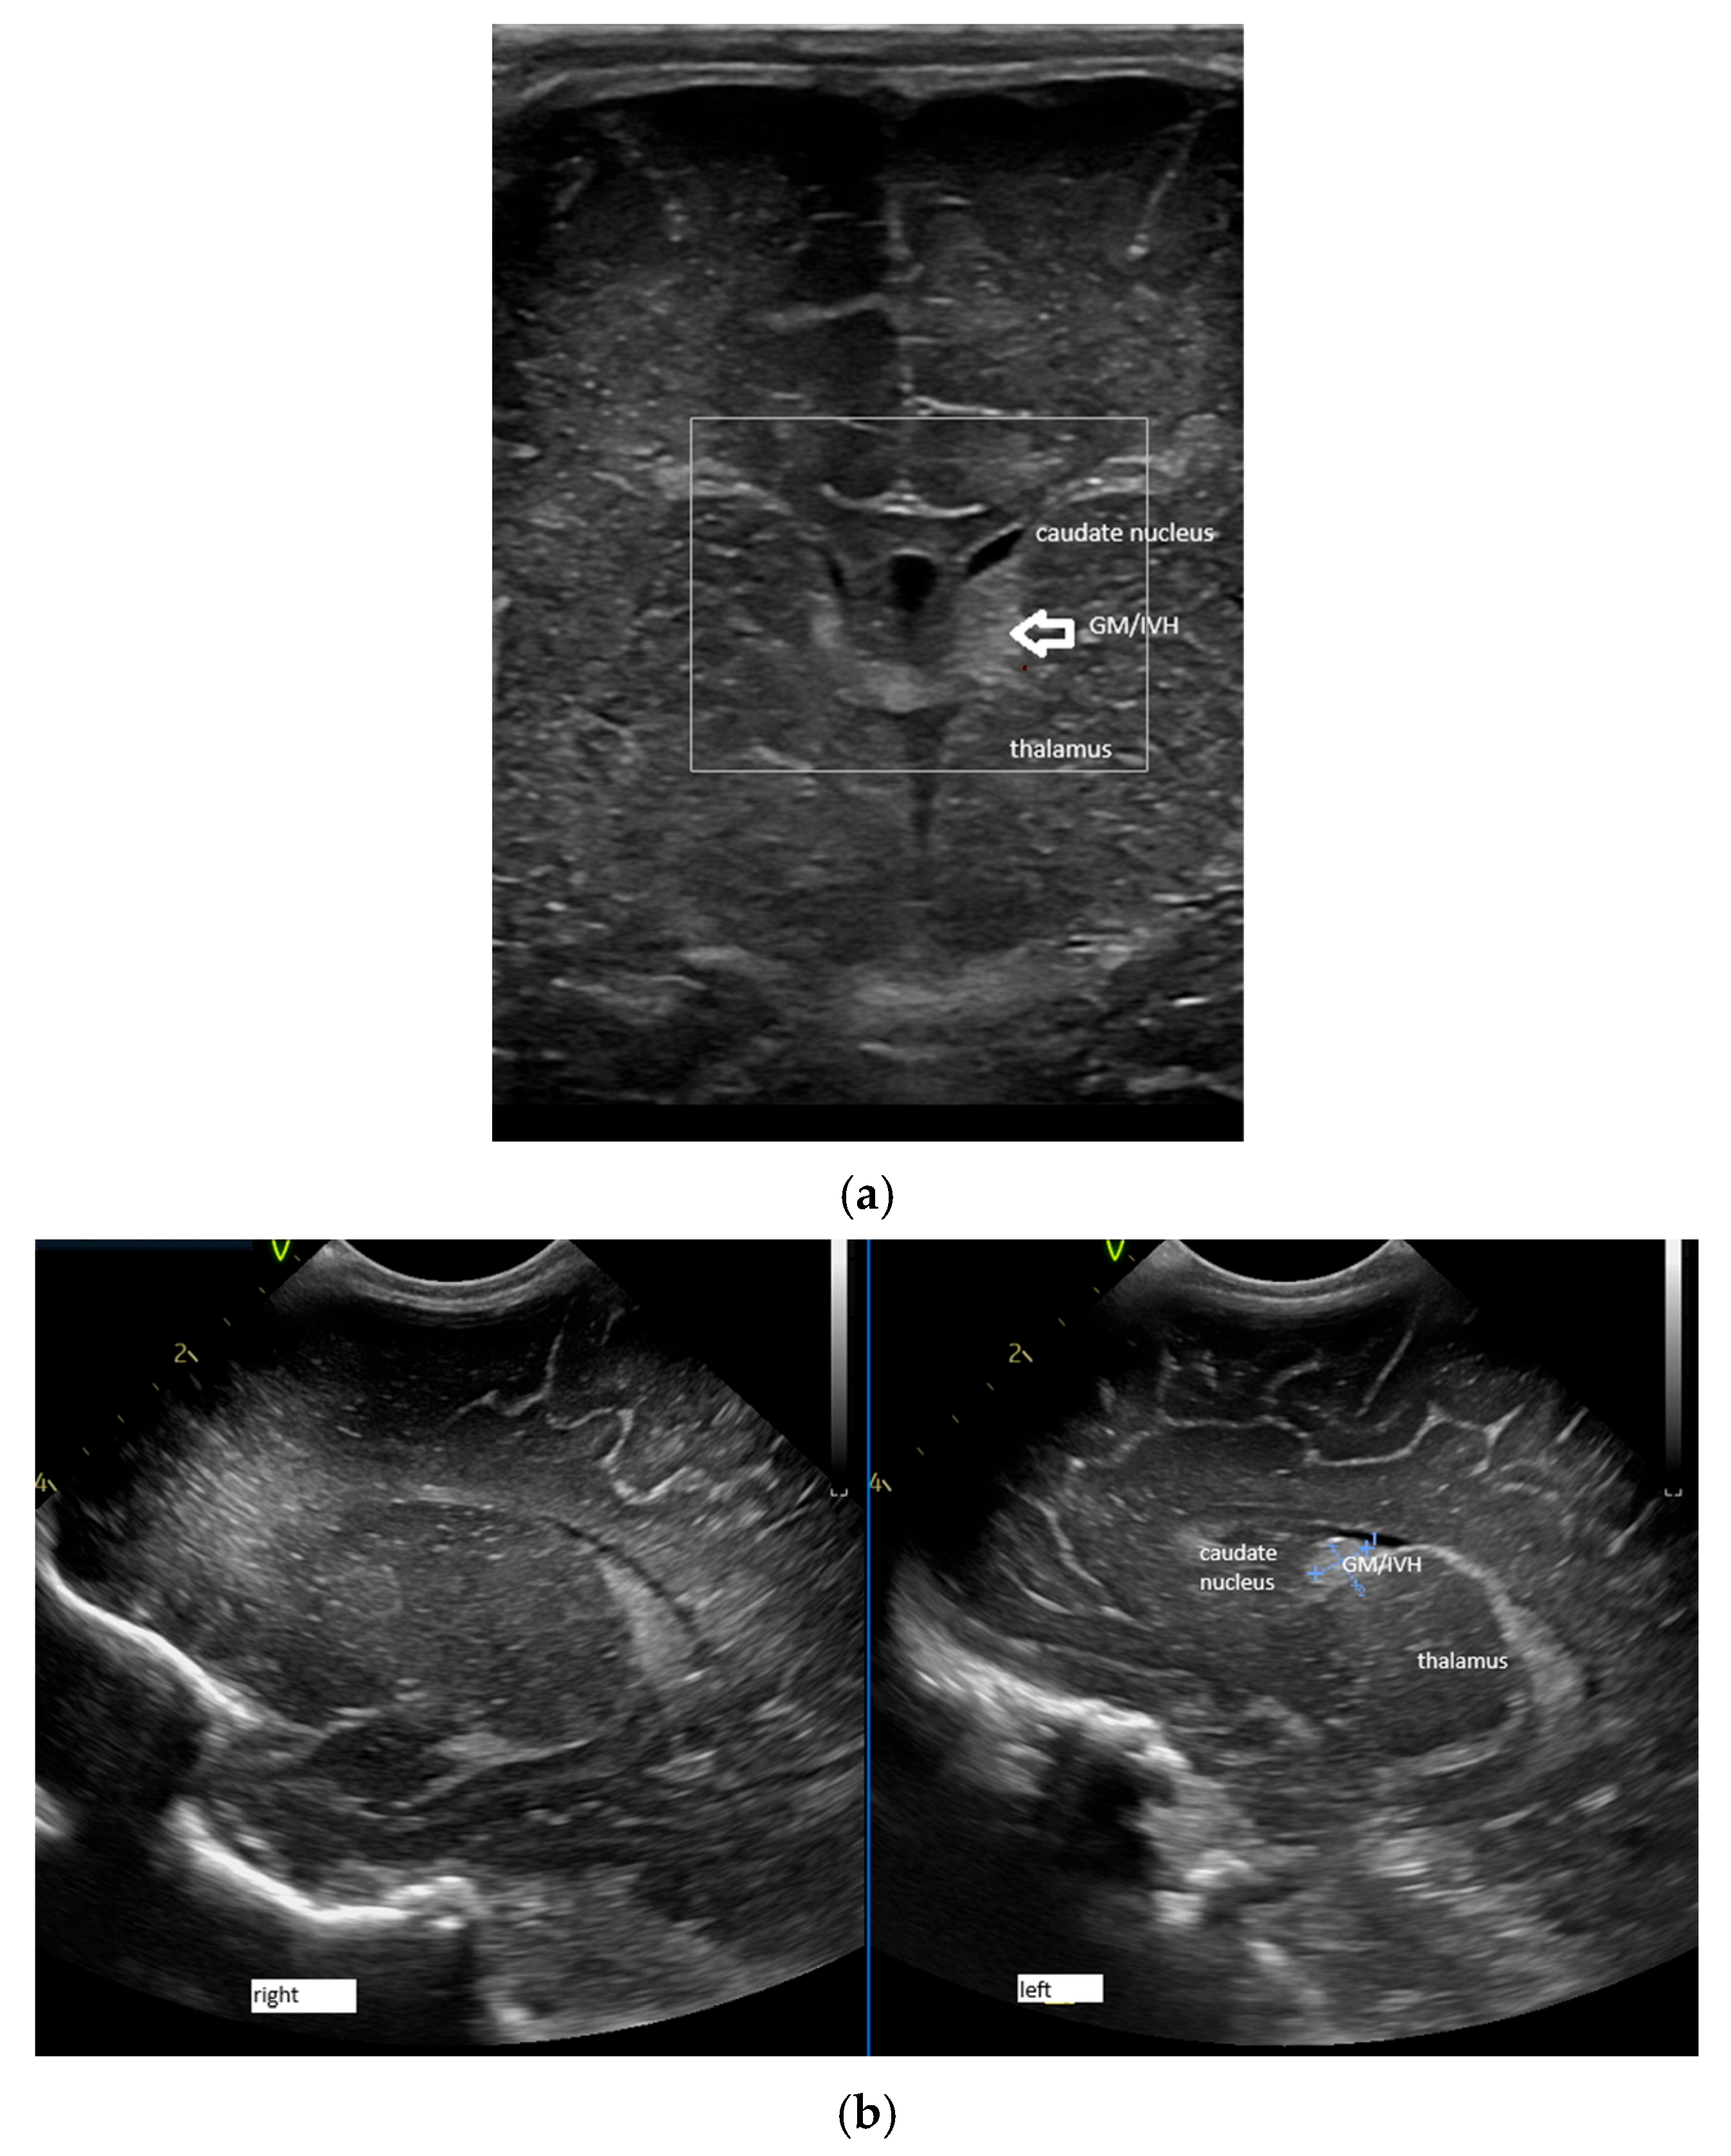

- A lack of identification of the confluence—wherein the terminal vein was absent on one or both sides—an example is the case presented in Figure 3, where the terminal vein was most probably draining in a direct lateral vein on the left side.